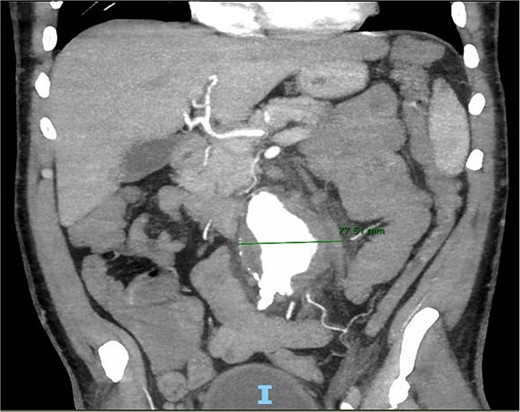

A 56-year-old male with no reported past medical history and a 70 pack year smoking history presented with a chief complaint of lower abdominal pain and body aches. On presentation, the patients white blood cell count (WBC) was 39.6 and procalcitonin was 43.4. Blood cultures were drawn and demonstrated P. mirabilis bacteremia. Computed tomography (CT) abdomen/pelvis was performed as well as ultrasound (US) of scrotum demonstrating a complex fluid collection within scrotal sac that was determined to be a scrotal wall abscess. The patient was started on a course of Unasyn and Urology promptly took him to the operating room (OR) for incision and drainage. Vascular surgery was consulted due to an incidental finding of an abdominal aortic aneurysm on CT measuring 4.7 × 4.6 cm (Figs 1 and 2). The patient was evaluated by the vascular surgery team following his urological procedure and denied any history of abdominal pain or back pain. Physical exam was largely unremarkable however the patient’s bilateral toes were noted to have blue discoloration with motor and sensation intact. Outpatient follow up with routine US scans for the AAA was recommended. Ankle brachial index (ABI) as well as an echocardiography was ordered to further work up the patient’s dusky toes. On Day 2 of hospitalization, ABIs returned showing severe peripheral vascular disease (PVD) and the echocardiography ruled out endocarditis. At this time an angiogram was planned to further the patient’s PVD workup however this was deferred as the patient remained septic with a WBC of 30. Over the course of the next few days the patient refused antibiotics and remained septic with a WBC in the 20s. At this time his toes quickly deteriorated from dusky to dry gangrene. On Day 8 of hospitalization the patient remained septic and was now complaining of new onset mid-abdominal pain. Emergent CT showed AAA was now 7.7 × 7.8 cm with periaortic fat stranding concerning for impending rupture (Figs 3 and 4). The patient was taken emergently to the OR for open repair. Upon visualization, the abdominal aortic aneurysm was clearly infected with signs of impending rupture on the left lateral wall and purulent material including infected thrombus. Tissue was cultured however showed no growth, likely due to the fact that the patient had been on antibiotic therapy for a week at this time. Reconstruction with an aorto-biiliac bypass using rifampin-soaked dacron graft was performed. A piece of omentum was mobilized over the graft and the retroperitoneum was closed over it. The abdomen was left open for a return to the OR for a second look which showed no concerns for bowel ischemia, worsening infection or bleeding. On post-op Day 5 the patient was extubated, off pressor support, and transferred to the floor. The patient’s postoperative course was unremarkable except for bilateral toes demarcating to dry gangrene.

Frontal CT angiography of the abdomen and pelvis demonstrating 7.75 cm AAA with fat stranding.